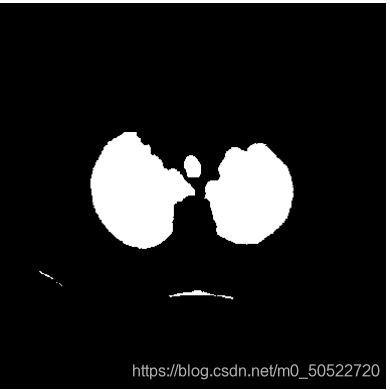

(5)肺质提取

由步骤4得到的图像肺质成像较好,但是肺质并没有与人体分离,此时就需要使用填充算法,首先将上图的图片进行二值图像孔洞填充,将整个人体组织填充,再使用填充后的图像减去上图中的图像就可以将肺质单独提取出来。